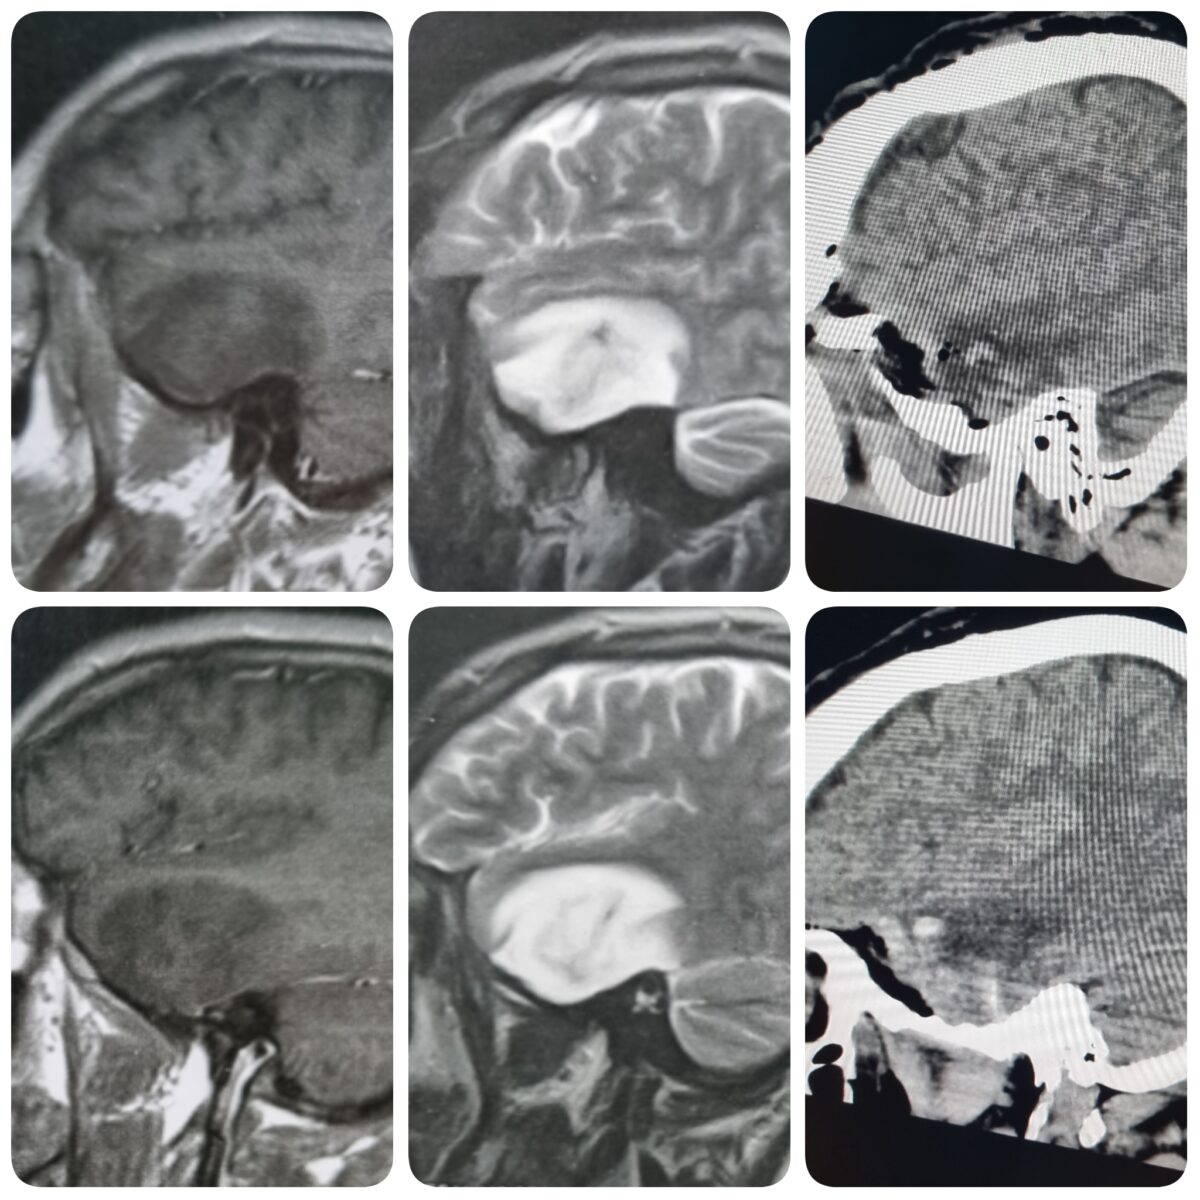

– الرنين المغناطيسي على المخ بالصبغة، والذي يظهر مكان الورم، ويساعد في التخطيط للجراحة، ويساعد في معرفة طبيعة الورم.

– الرنين المغناطيسي الطيفي، والذي يساعد في معرفة طبيعة الورم ودرجته من حيث قدرته على النمو والارتجاع بعد الجراحة.

أمثلة لاستئصال أورام داخل نسيج المخ بالجراحة الميكروسكوبية